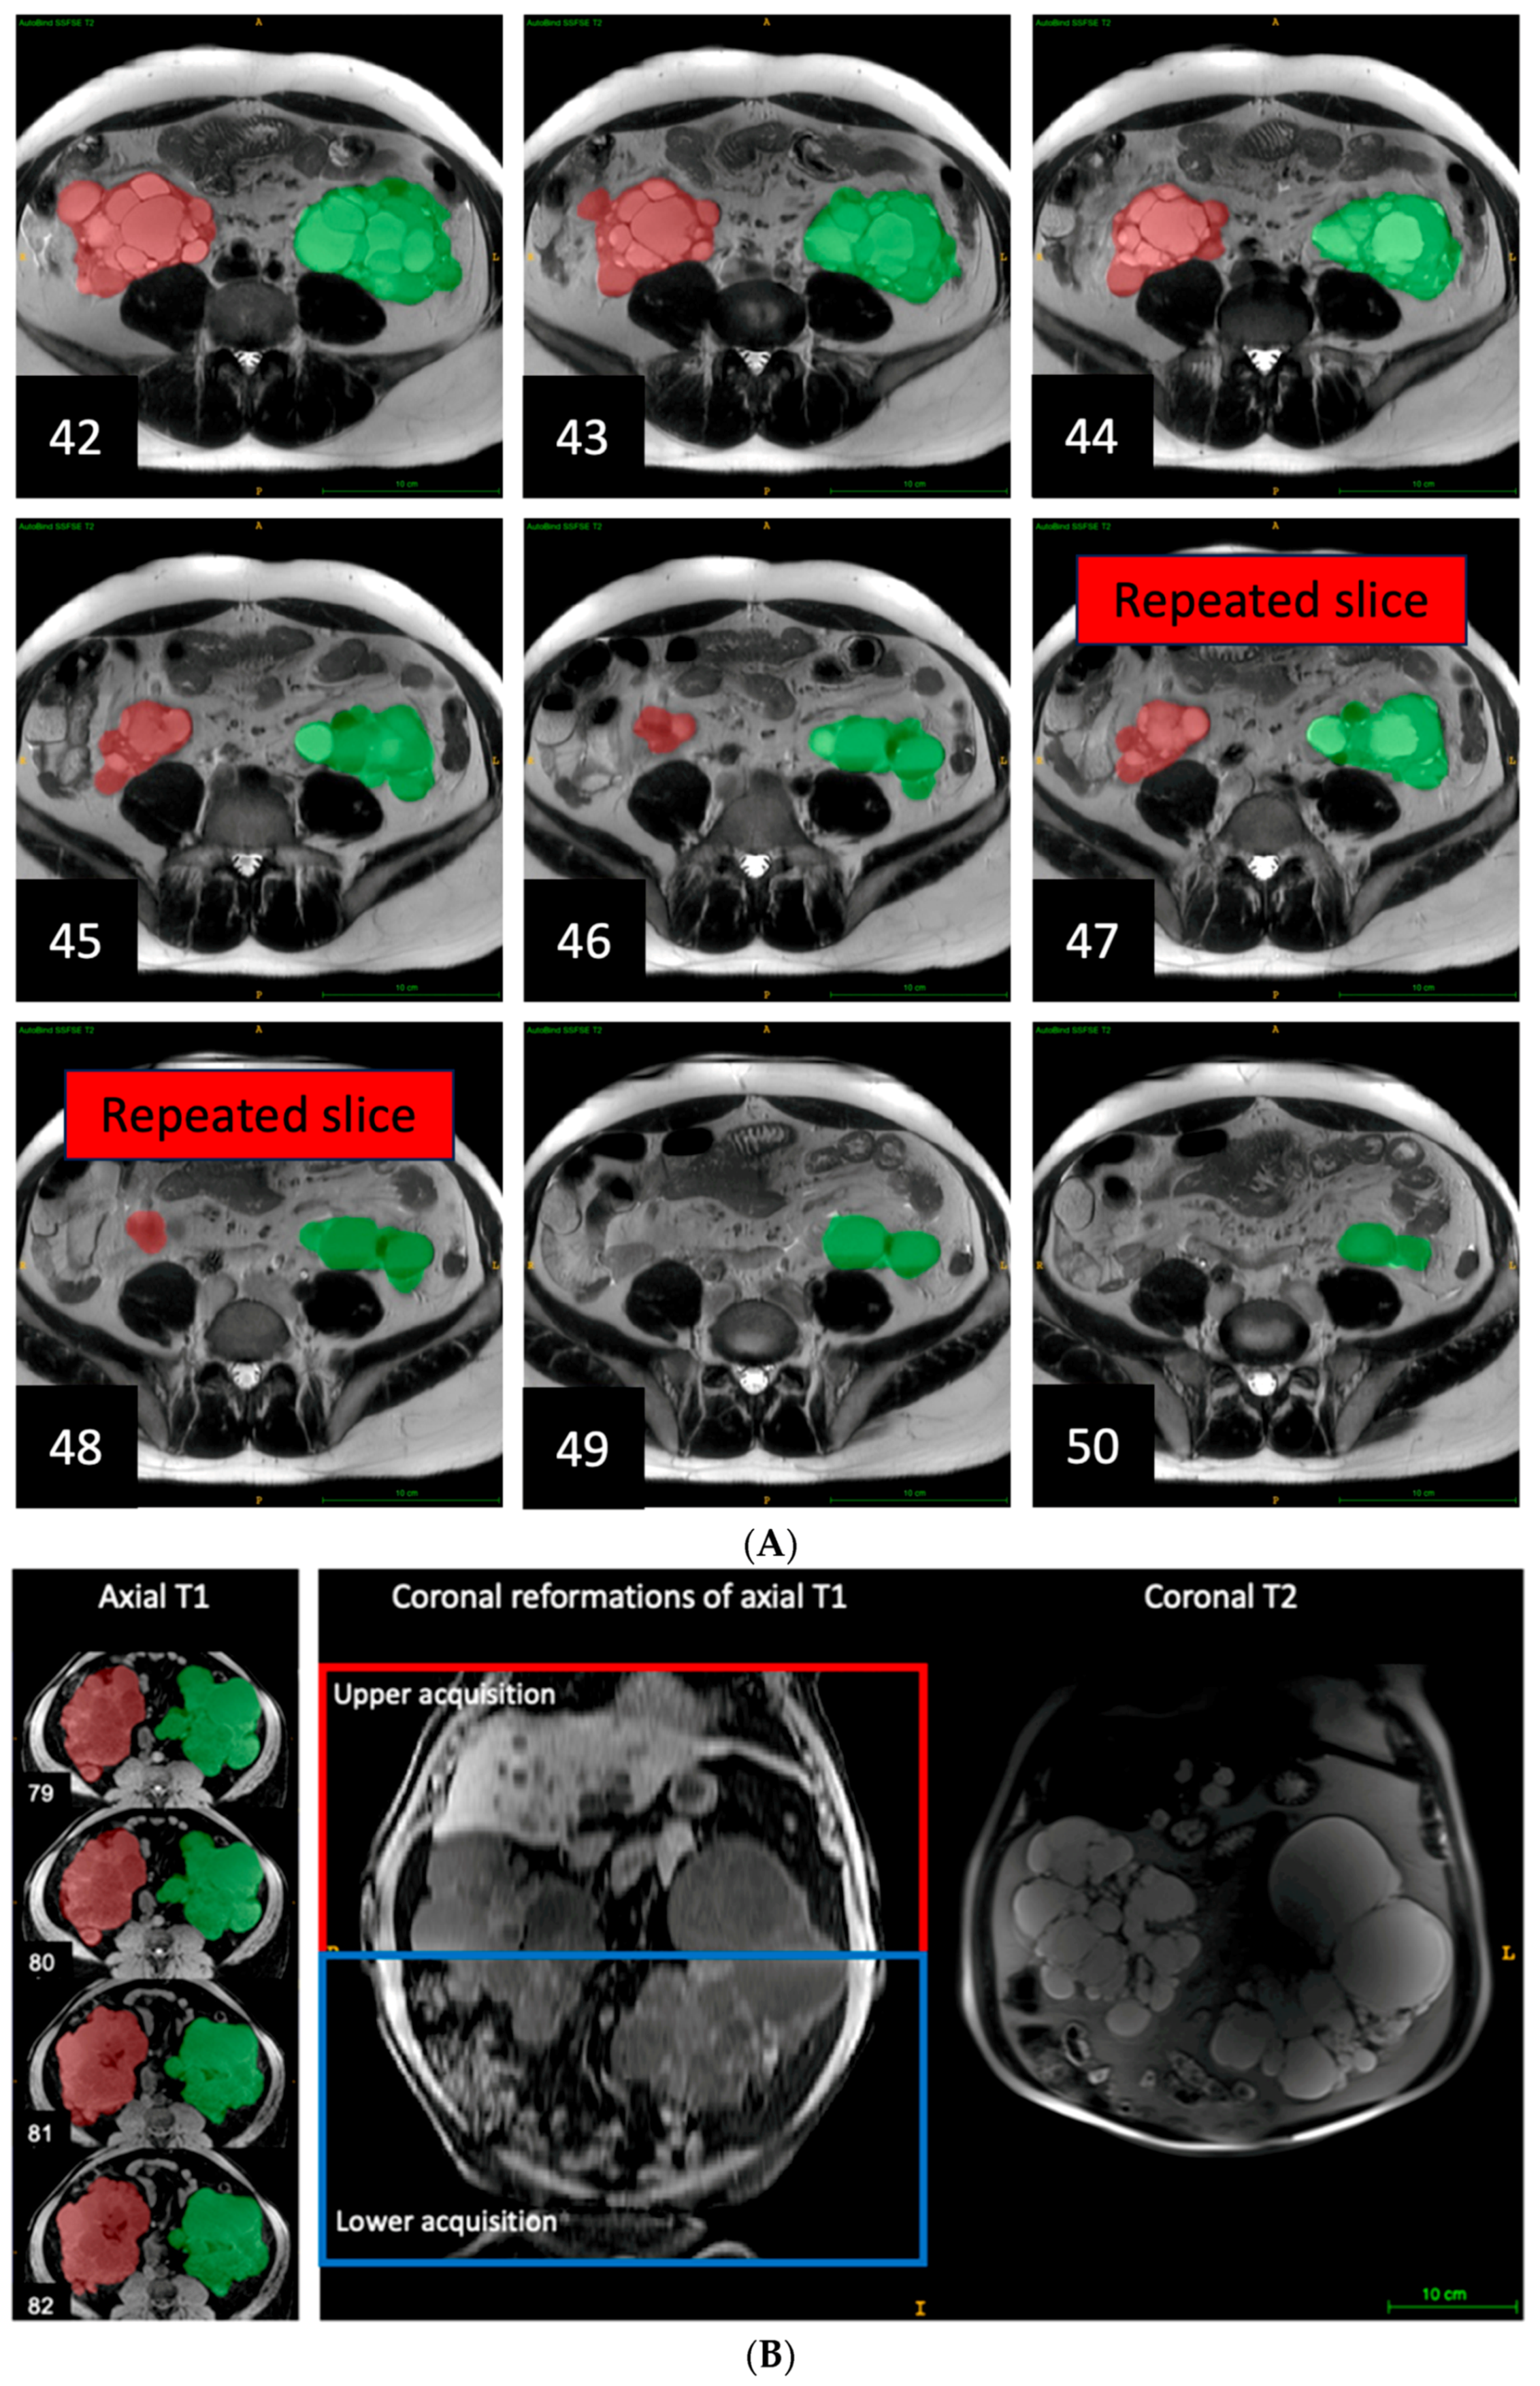

Errors arising from using multiple breath holds at different breath-hold positions to complete an axial acquisition manifested as nearly duplicated or missing kidney slices, and uneven body boundaries on coronal, or sagittal reformations (Figure 4). Additionally, duplicated or missing kidney slices commonly occurred in the middle of the acquisition. This error was observed in 25 axial sequences, accounting for 5% of sequences and 19% of the exams causing a median TKV underestimation of 4.4% relative to the reference TKV, with percent differences ranging from −12% to 22%. Notably, axial T1 sequences represented nearly half of all pulse sequences with this error and mostly resulted in underestimation, with a median of −6.1% and an interquartile range of −7.4% to 4.4%.

Figure 4. (A). Duplicated images due to acquiring images 1 to 46 during one breath hold and images 47 to 92 with another breath hold at a different respiratory position. This causes images 47 and 48 to overlap with images 45 and 46. This can be corrected by deleting images 47 and 48 which changes the TKV 3741 mL, pre-correction, to 3592 mL after correction; This 4.0% change brings the TKV measurement for this sequence more in line with TKV measured on the other sequences. Right kidney is labeled in red. Left kidney is labeled in green. (B). Missing images of axial T1 due to acquiring images 1 to 80 during one breath hold and images 81 to 160 with another breath hold at a different respiratory position. This causes a substantial change in kidney slice morphology between images 80 and 81 in axial T1, and a discontinuity in the coronal reformations of axial T1, which was not seen in the coronal T2. This error led to a 3.2% underestimation of TKV compared to the reference TKV.